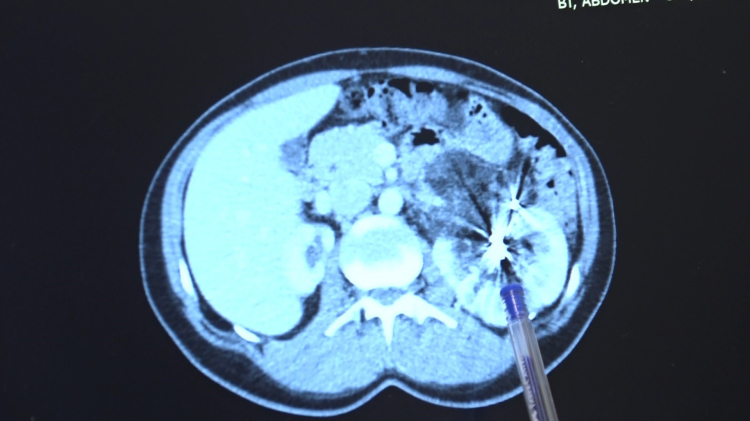

Zorlu bir ameliyatı başarıyla tamamlayan Bursa Medicana Hastanesi Üroloji Uzmanı Doç. Dr. Ahmet Şahan, hastanın durumunun şuan iyi olduğunu belirterek, “Nurcan Hanım 35 yaşında bize İzmir'den geldi. Doğuştan tek böbrekli bir böbreği küçük olduğu için işlevsiz durumda. Sağlam böbreğinde ise 2016'da tanısı konmuş giderek büyüyen iyi huylu "anjiomyolipomu" denilen 12 santimetre boyutunda bir kitlesi var. Bu kitle artık böbreğin damarlarını içerisine almış komplike bir kitle durumunda. Hastaya iki kez anjioembolizasyon tedavisi uygulanmış fakat başarısız olduğu için kitle büyümeye devam etmiş. Kadınlarda 4 santimetreden büyük anjiomyolipomular kendiliğinden kanayarak yaşamı tehlike altına attığı için bu kitlelerin alınması gerekiyor. Tek böbrekli olunan durumlarda böbreğin tamamen alınması durumu da söz konusu olabiliyor. Bu riske girmemek için çoğu merkez de embolizasyona başvurmuş. Hasta bize geldiğinde bu işi yapabileceğimizi söyledik. 2 saat süren kapalı bir ameliyatla kitleyi tamamen çıkardık ve hastamızı 3 gün içerisinde taburcu ettik. Hastamızın değerli şuan iyi durumda. Hastamızı diyalizden kurtarıp kapalı bir ameliyatla sağlığına kavuşturabildiğimiz için çok mutluyuz” dedi.